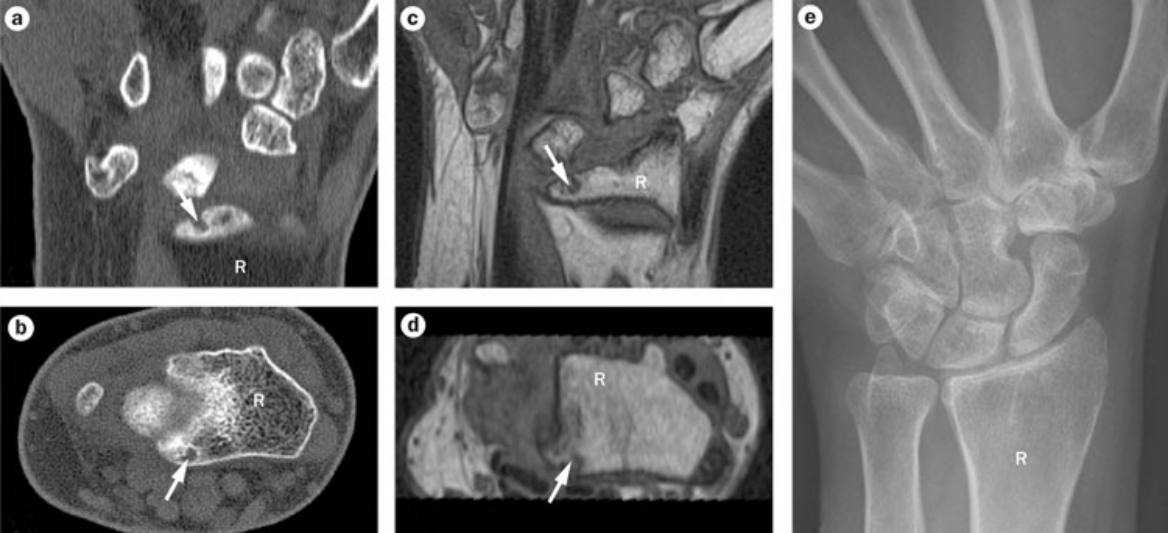

X线和MRI

◆ MRI的优点:敏感,骨髓水肿,软骨,滑膜,骨质破坏

◆ MRI的缺点:昂贵,单或对称部位,需充分镇静,完成时间久